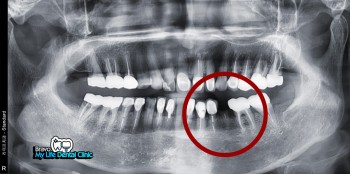

멀티플 임플란트 시술

임플란트를 통한 전체적인 치아복원 케이스